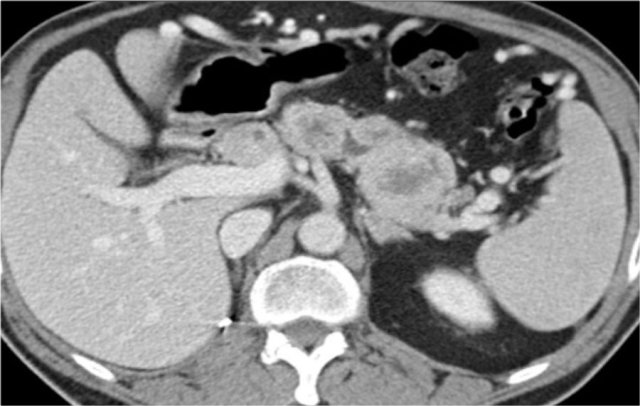

In this case there are hypodense areas in both kidneys.

Based on the imaging alone the main differential is multifocal pyelonephritis, lymphoma and metastases.

This patient had a urinary tract infection and episodes of flank pain and there was no history of a primary tumor or lymphoma.

So the diagnosis is pyelonephritis.

A CT scan 4 months later shows normal enhancement of both kidneys; the renal abnormalities on the first scan were therefore consistent with an episode of multifocal pyelonephritis.